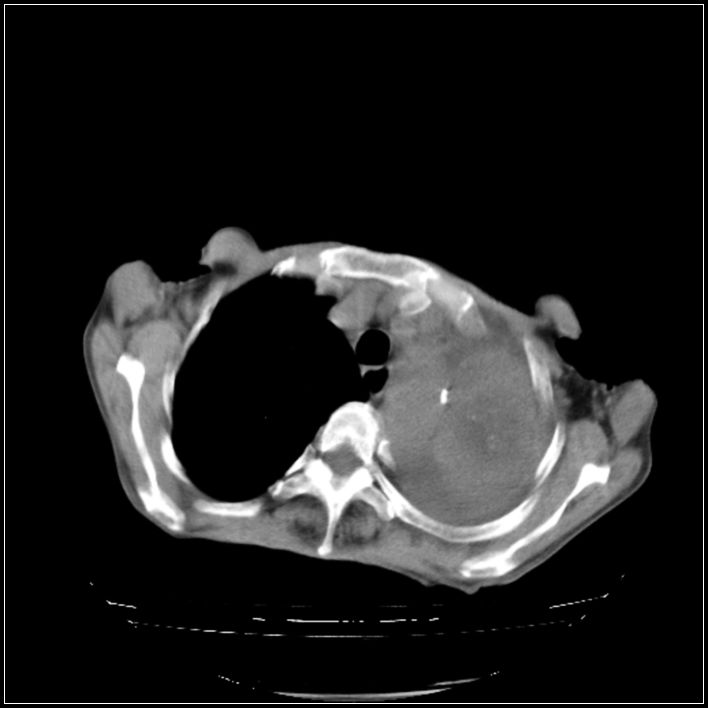

以下是引用影象小辈在2008-5-31 16:25:00的发言:[br]左侧胸腔团状不规则致密影,界欠规整,密度不均匀,其内可见更低密度影及高密度影,并可见包裹性胸腔积液 考虑为1.畸胎瘤 2.肺癌